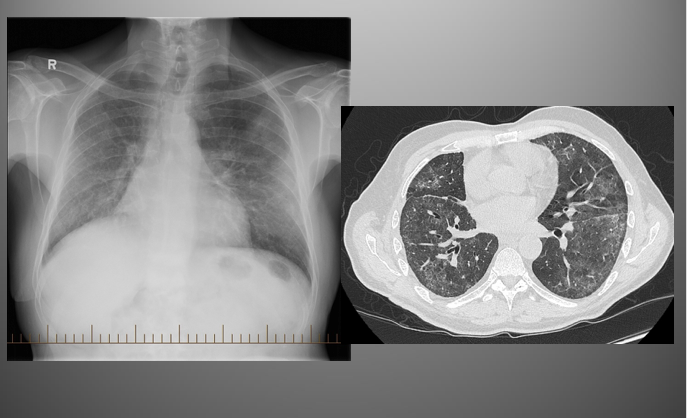

What’s your diagnosis?

Lobar Pneumonia: right middle lobe